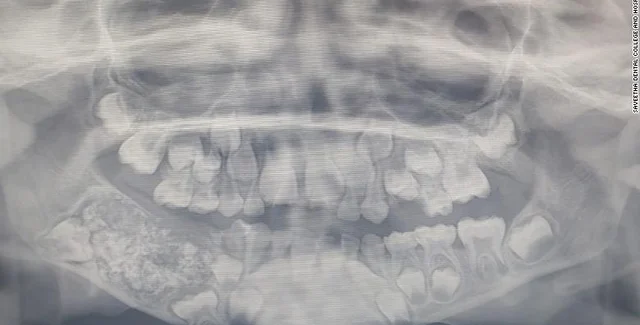

Мальчик был госпитализирован в южном городе Ченнаи из-за отека и болей в нижней челюсти. На рентгене врачи увидели в нижней челюсти мальчика мешок, заполненный недоразвитыми зубами.

Рентген челюсти ребенка. Фото: Saveetha Dental College and Hospital